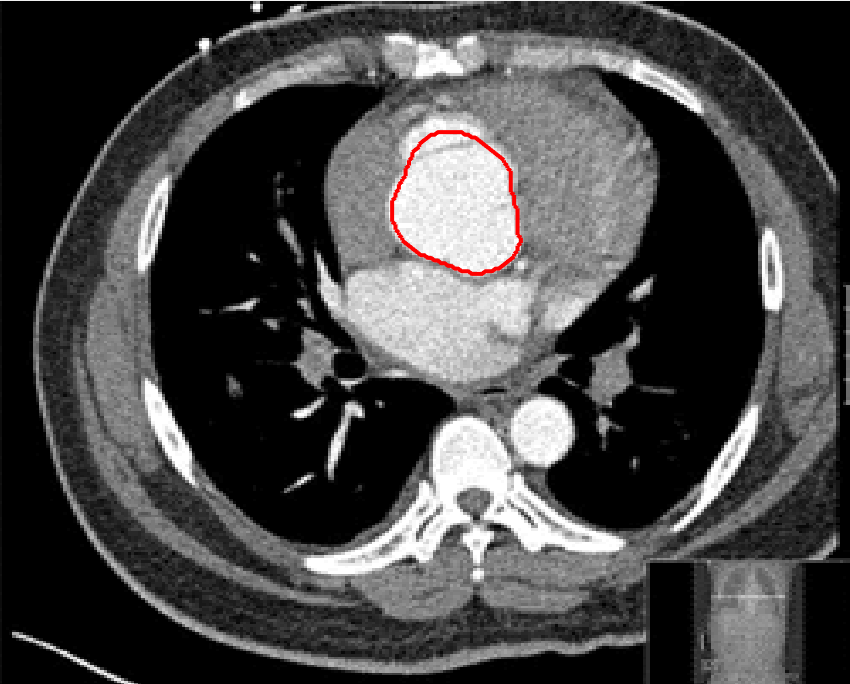

Four sets of test results are shown below. In Test 1 we compare models M1 – M6 to the proposed model M7 for two images which are hard to segment. The first is a CT scan from which we would like to segment the lower portion of the heart, the second is an MRI scan of a knee and we would like to segment the top of the Tibia. See Figure 9 for the test images and the marker sets used in the experiments. In Test 2 we will review the sensitivity of the proposed model to the main parameters. In Test 3 we will give several results achieved by the model using marker and anti-marker sets. In Test 4 we show the initialisation independence and marker independence of the Geodesic Model on real images.

Refer to captionRefer to captionRefer to captionRefer to caption

(i)                                 (ii)                                 (iii)                                 (iv)

Figure 9: Test 1 setting: (i) Image 1;  (ii) Image 1 with marker and anti-marker set shown in green and pink respectively;  (iii) Test Image 2; (iv) Image 2 with marker set shown.